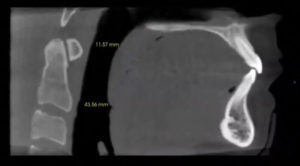

18% of general practitioners in the US are placing implants. Accuracy is significantly increased when armed with CBCT, eliminating contingency treatment plans and surprises during implant surgery. Prior to having these systems, many practitioners were handling implant placement freehand. Medically, you are on much firmer ground when you have cone beam in place. It’s akin to having GPS technology: you know the size, what brand, and where to place the implant in the patient’s mouth.

The CBCT measures an exact one-to-one ratio with no superimposed structures or magnification. This way, you can precisely measure in between implants to ensure you have the proper room from one implant to another, and you can assess the bone quality and quantity. Specialists can place a single implant in roughly 15 minutes if they are well prepared.